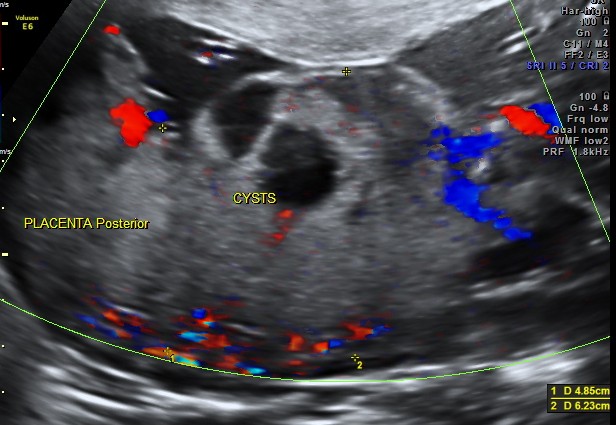

Placentomegaly with placental cysts